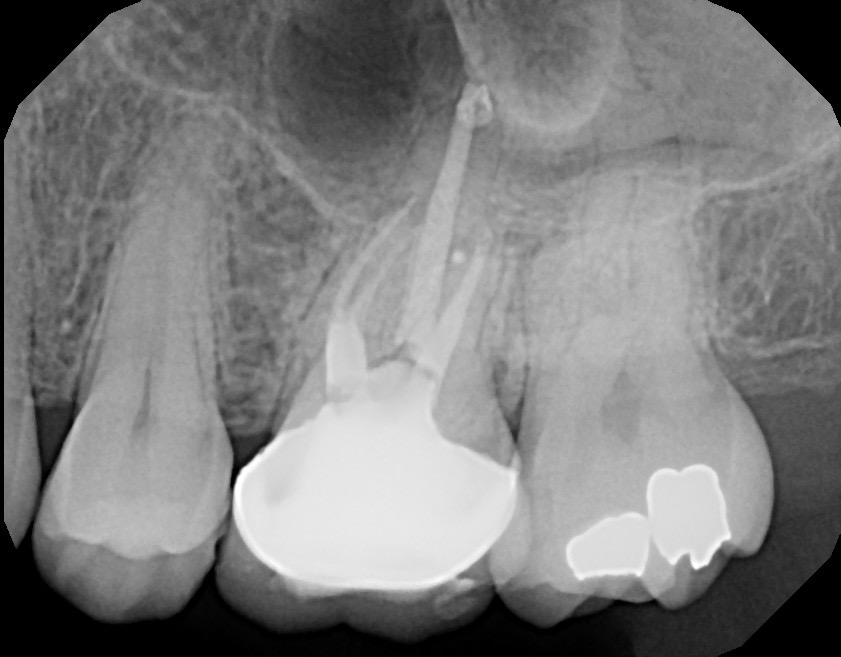

Tooth #14 completed showing file removed and MB and MB2 obturated.